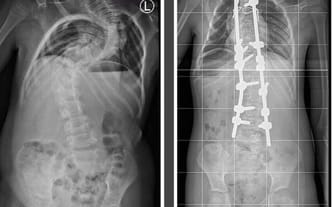

Było fajnie, wyprostowało się. Można było się cieszyć, że można iść, chodnikiem, czy łąką.. powoli ale jednak.. jak wszyscy.

Ale... się skrzywiło. Trochę... potem mocniej... a terez mocno.